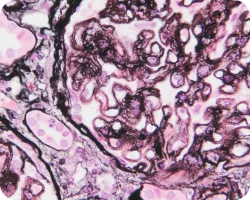

Сегментарный гломерулосклероз (более четырех мезангиальных клеток):

Сегментарный гломерулосклероз

Признаки гипертрофии подоцитов или склероз с локализацией на канальцевом полюсе, являющиеся одной из причин сегментарного гломерулосклероза, связаны с более выраженной протеинурией и более быстрым снижением функции почек. Вместе с тем у пациентов, имеющих описанные признаки, иммуносупрессивная терапия связана с лучшей почечной выживаемостью22.